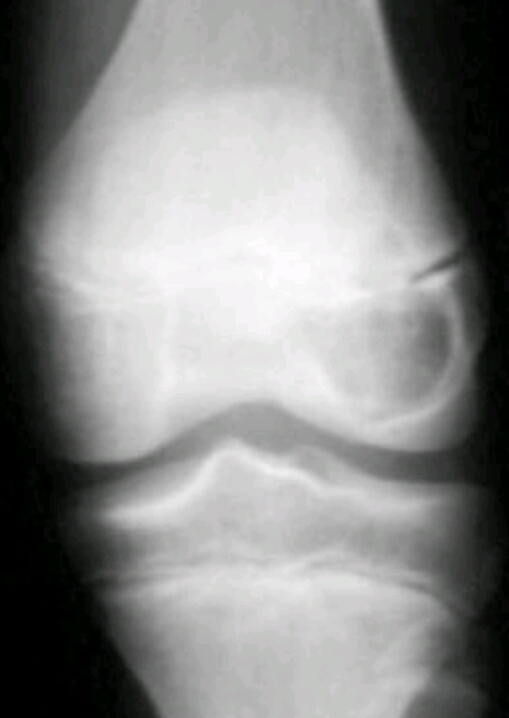

Findings? Diagnosis?

Geographic, eccentric, metaphyseal/epiphyseal, subarticular, soap bubble appearance, lytic, cortical thickening

Giant cell tumor